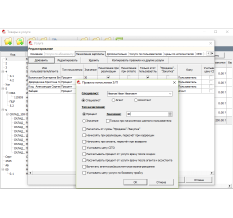

Инструмент «все в одном»Он способен управлять различными устройствами для биомеханического анализа, хранить все данные в единой базе данных и предоставлять обзор анализов пациента.

Создание автоматических отчетов, основанных на научных изысканиях, поддерживающие все виды профессиональных данных, преобразованные в четкие и понятные заключения.